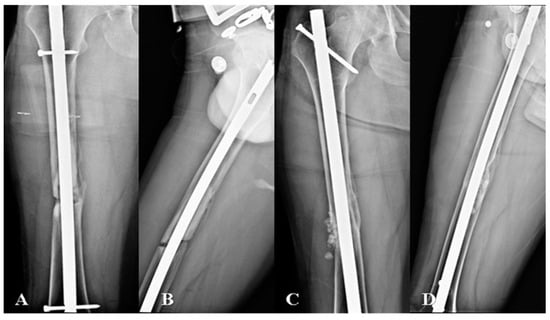

2.4.1. Nail Exchange Technique

2.4.2. Plate Augmentation with Autologous Bone Grafting Technique